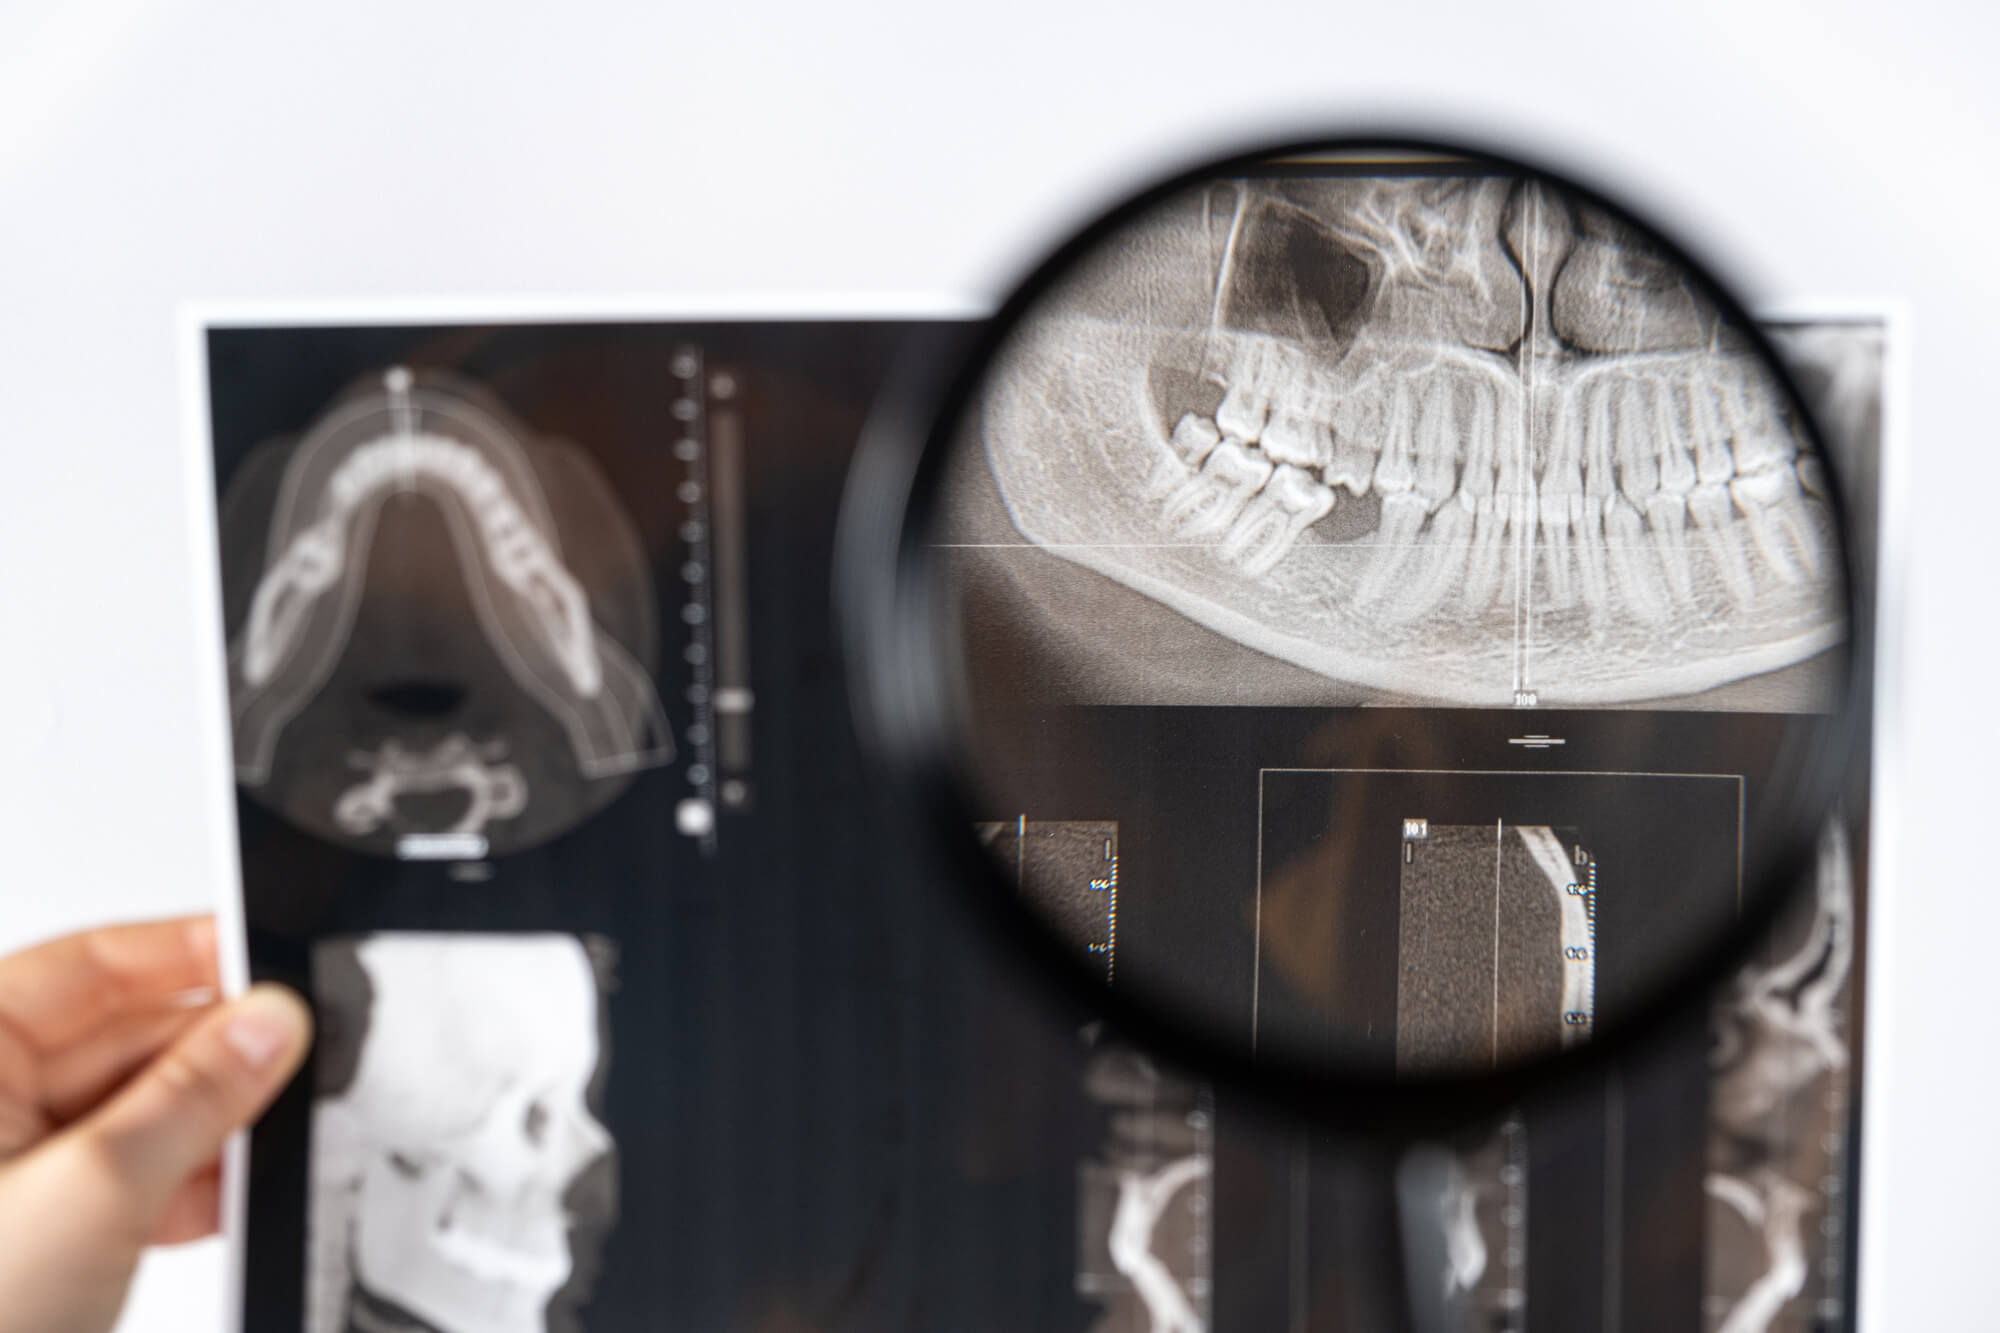

歯科用CTは、コンピュータを利用した画像処理により、口腔およびその周辺の3次元画像を再構成し、診断に使用される装置です。

X線を使ってさまざまな角度から詳細な画像を取得することで、インプラント治療をはじめとする各種歯科治療において重要な情報を提供します。

歯の状態や骨の厚み・高さ、神経や血管の位置を正確に把握することが可能で、より安全に精度の高い診療を実現します。

従来のレントゲンは平面画像をもとに情報を得るため、奥行きや骨の詳細な状態を把握することが難しい一方、歯科用CTは三次元の立体画像を生成します。

通常のレントゲンでは確認できない骨内部の状態や神経、血管の走行まで詳細に把握できます。これまでの平面的な画像よりも詳細な情報が得られるため、骨や神経の位置関係を正確に理解でき、治療の精度が飛躍的に向上します。

従来のレントゲンでは平面的にしか把握できなかった骨の内部構造や、歯周病の進行具合、親知らずの状態なども、歯科用CTでは立体的に確認することができます。

インプラントの埋入位置を正確に決定するための検査や、骨密度を測定して柔軟性を確認することができ、患者様それぞれの口腔内の状態に応じた適切な治療を可能にします。

前述した通り、歯科用CTを使用すると、従来の2次元画像では困難であった3次元的な診断が可能になります。これにより、骨や神経の位置、血管の配置、骨密度など、口腔内の詳細な情報を把握し、より精密な診断が行えます。

立体的な3D画像は患者様に対する説明も可視化されることで理解しやすく、安心感も高まるでしょう。